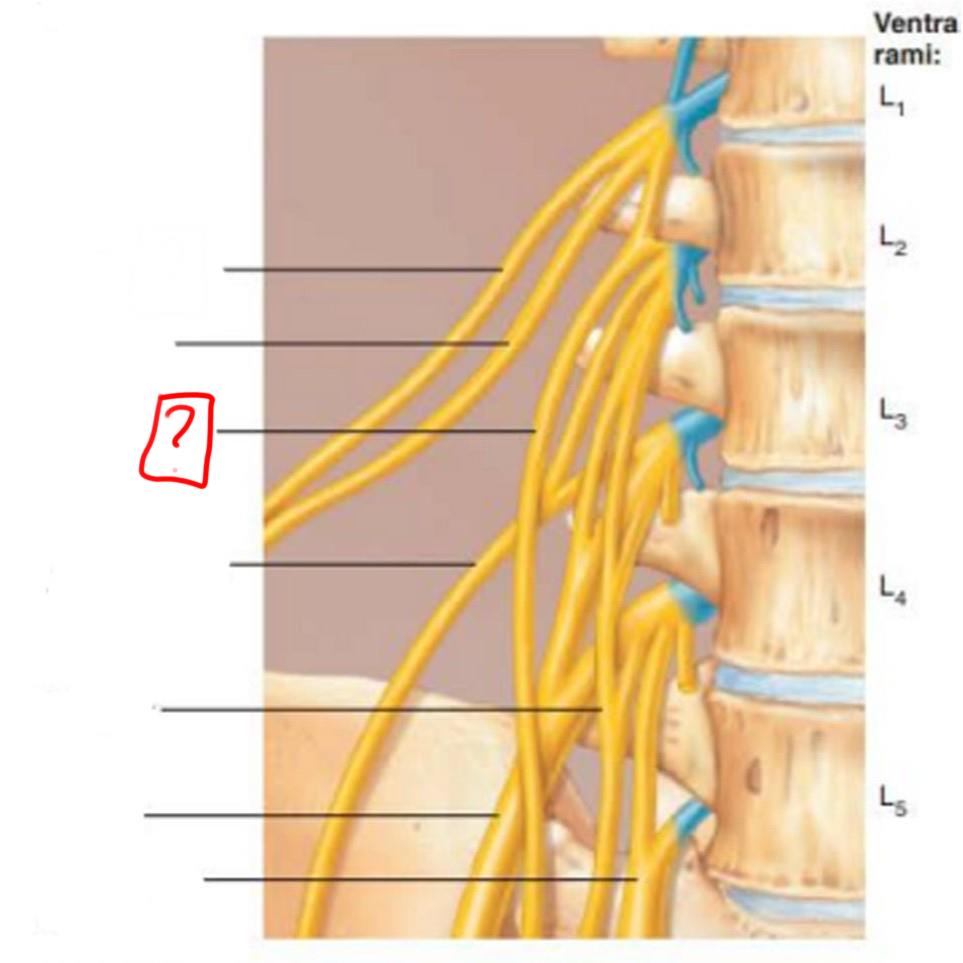

lumbar plexus

L1-L4

major nerves: ilioinguinal, obturator, femoral, genitofemoral

iliohypogastric

ilioinguinal

genitofemoral

lateral femoral cutaneous

obturator

femoral

lumbosacral trunk